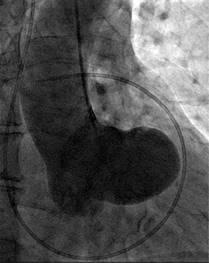

The cardiac catheterization presented normal coronaries with a small right coronary artery. The left ventricular angiogram presented inferior mild hypokinesia, and the aortogram revealed an abnormal appearance which we described as «a boot in the heart», produced by the severely dilated non-ruptured right sinus of Valsalva without fistulous tracts (Figure 4).

Figure 4: Aortogram.